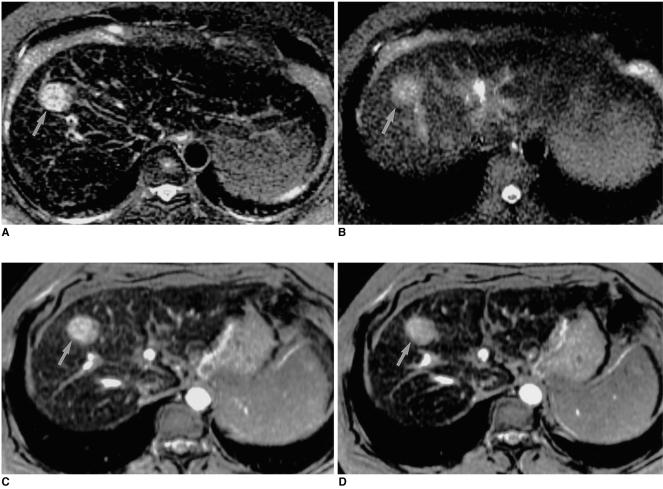

Sixteen patients with 25 HCCs underwent MR imaging following intravenous infusion of ferumoxides. All MR studies were performed on a 1.5-T MR system, using a phased-array coil. Ferumoxides (Feridex IV) at a dose of 15 micromol/Kg was slowly infused intravenously, and axial images of seven sequences were obtained 30 minutes after the end of infusion. The MR protocol included fast spin-echo (FSE) with two echo times (TR3333-8571/TE18 and 90-117), singleshot FSE (SSFSE) with two echo times (TRinfinity/TE39 and 98), T2*-weighted gradient- recalled acquisition in the steady state (GRASS) (TR216/TE20), T2*-weighted fast multiplanar GRASS (FMPGR) (TR130/TE8.4-9.5), and T2*-weighted fast multiplanar spoiled GRASS (FMPSPGR) (TR130/TE8.4-9.5). Contrast-to-noise ratios (CNRs) of HCCs determined during the imaging sequences formed the basis of quantitative analysis, and images were qualitatively assessed in terms of lesion conspicuity and image artifacts. The diagnostic accuracy of all sequences was assessed using receiver operating characteristic (ROC) analysis.

Quantitative analysis revealed that the CNRs of T2*-weighted FMPGR and T2*-weighted FMPSPGR were significantly higher than those of the other sequences, while qualitative analysis showed that image artifacts were prominent at T2*-weighted GRASS imaging. Lesion conspicuity was statistically significantly less clear at SSFSE imaging. In term of lesion detection, T2*-weighted FMPGR, T2*- weighted FMPSPGR, and proton density FSE imaging were statistically superior to the others.

T2*-weighted FMPGR, T2*- weighted FMPSPGR, and proton density FSE appear to be the optimal pulse sequences for ferumoxidesenhanced MR imaging in the detection of HCCs.

16例患有25个HCC的患者在静脉输注超顺磁性氧化铁后接受MR成像。所有MR检查均在1.5-T MR系统上使用相控阵线圈进行。以15 μmol/Kg的剂量缓慢静脉输注超顺磁性氧化铁(Feridex IV),输注结束30分钟后获取7个序列的轴位图像。MR检查方案包括具有两个回波时间(TR3333 - 8571/TE18和90 - 117)的快速自旋回波(FSE)、具有两个回波时间(TR无穷大/TE39和98)的单次激发FSE(SSFSE)、稳态下的T2加权梯度回波采集(GRASS)(TR216/TE20)、T2加权快速多平面GRASS(FMPGR)(TR130/TE8.4 - 9.5)以及T2*加权快速多平面扰相GRASS(FMPSPGR)(TR130/TE8.4 - 9.5)。成像序列中测定的HCC的对比噪声比(CNR)构成定量分析的基础,并根据病变清晰度和图像伪影对图像进行定性评估。使用受试者操作特征(ROC)分析评估所有序列的诊断准确性。

定量分析显示,T2加权FMPGR和T2加权FMPSPGR的CNR显著高于其他序列,而定性分析表明T2加权GRASS成像时图像伪影明显。SSFSE成像时病变清晰度在统计学上明显较差。在病变检测方面,T2加权FMPGR、T2*加权FMPSPGR和质子密度FSE成像在统计学上优于其他成像。

T2加权FMPGR、T2加权FMPSPGR和质子密度FSE似乎是超顺磁性氧化铁增强MR成像检测HCC的最佳脉冲序列。